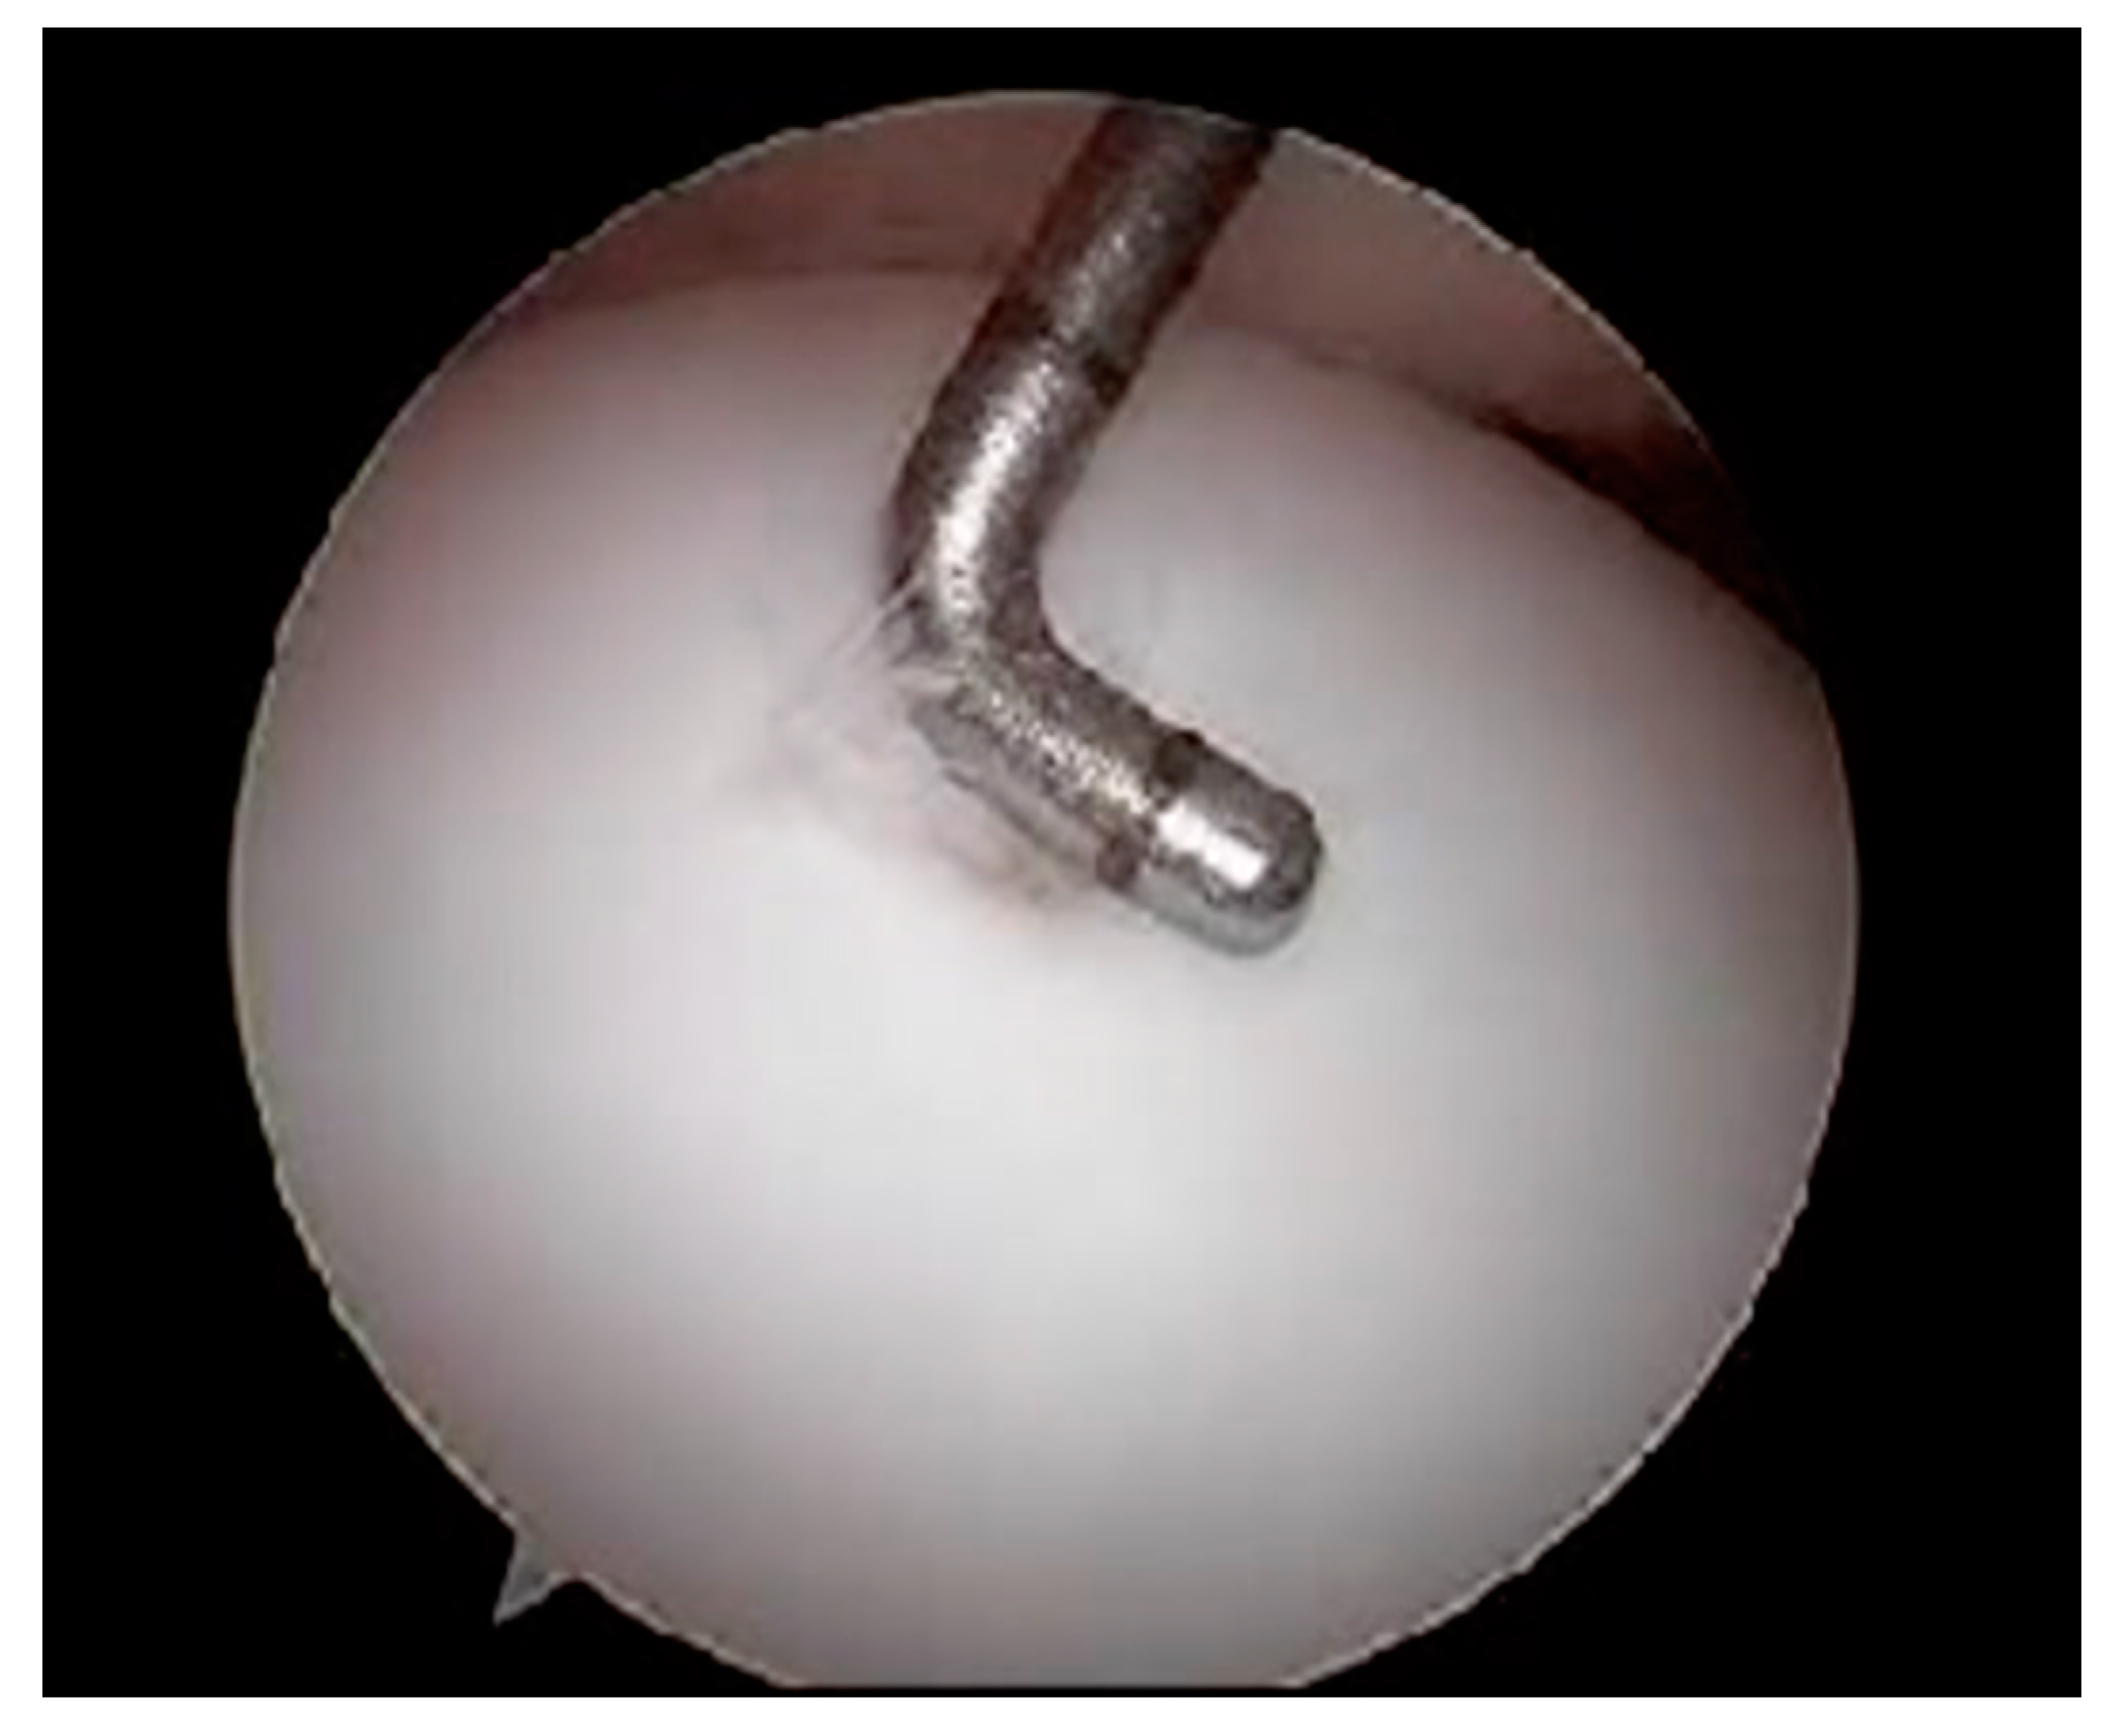

- Softening of the articular surface (Figure 2)

- Thermal chondroplasty